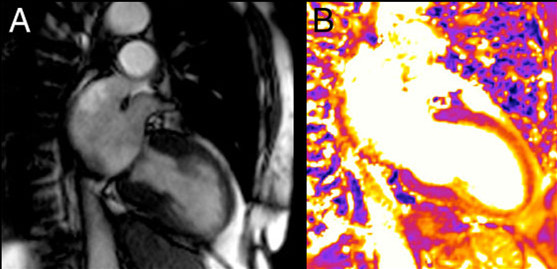

心脏收缩动态磁共振成像(MRI)显示了一名81岁TCM患者典型的心尖气球样扩张(A)。同一患者的心血管MRI(CMRI)T 2(横向弛豫时间)像显示心尖心肌T2信号强度升高[橙色](B)。这两个两腔位图像是在最初诊断TCM后3天获取的,患者在全身发作后出现短暂的心电图(ECG)改变和肌钙蛋白水平升高。

图像显示了81岁TCM患者发病3天后的两腔CMRI影像(幻灯片3是同一患者)。

左图:传统T2加权短时间反转恢复序列(STIR)快速自旋回波图像,可见心肌心尖信号强度增加,难以与缓流时管腔内血流信号进行区分。

右图:LGE 图像排除心肌瘢痕。